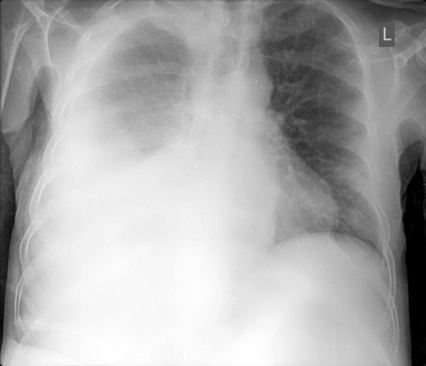

16

Q

Diagnose?

A

Højresidig basal pneumoni